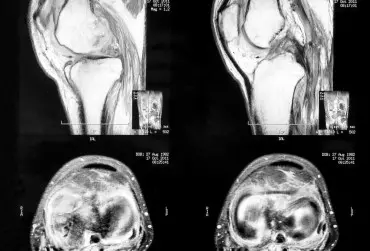

Postępowanie fizjoterapeutyczne w chondromalacji rzepki

Mianem chondromalacji często określa się zespół objawów klinicznych, jednak to pojęcie odnosi się do nieprawidłowości występujących w obrębie chrząstki stawowej – najczęściej rzepki. Rzepka (łac. patella) pełni funkcję ochronną stawu kolanowego od przodu, zwiększa również działanie mięśnia czworogłowego uda poprzez zwiększenie kąta ścięgna w stosunku do przyczepu na kości piszczelowej.